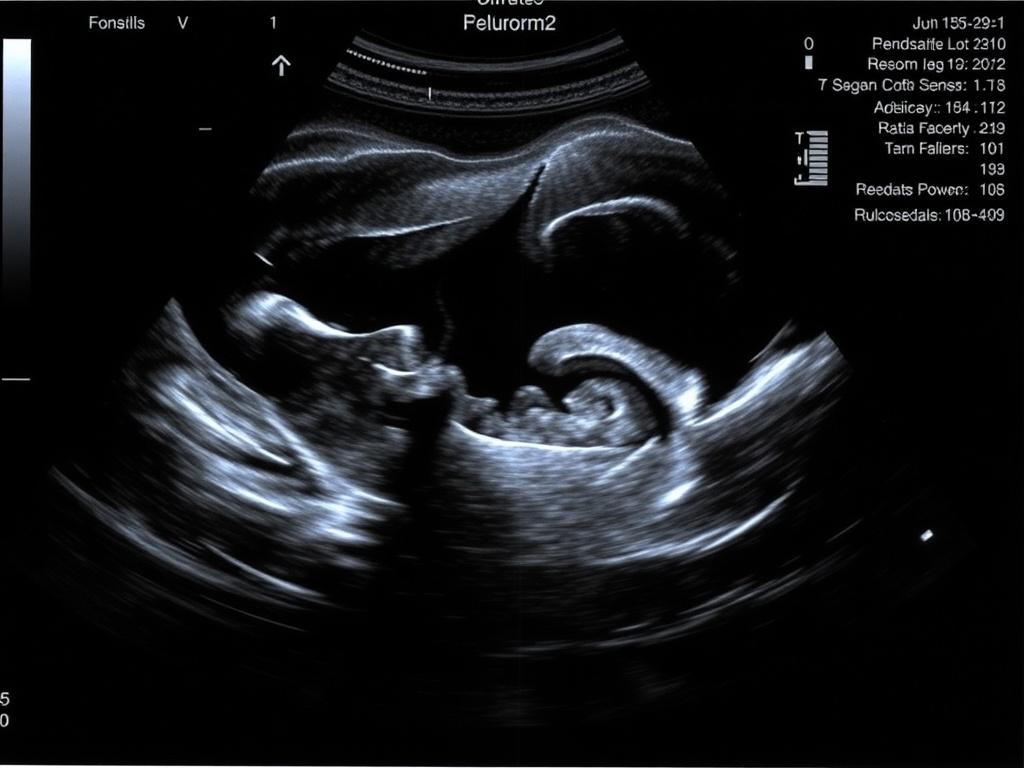

Ультразвук — это звуковые волны высокой частоты, которые отражаются от тканей и возвращаются к датчику. Компьютер преобразует эти отражения в изображение. УЗИ органов малого таза не дает радиации, быстр и безопасен. В органах малого таза ультразвук показывает форму, размеры, структуру органов и наличие жидкостных полостей. При использовании допплерографии можно оценить кровоток, а 3D-режим помогает получить объёмное представление об органе.

Список показаний длинный, но основные причины выглядят так: боли внизу живота, нарушения менструального цикла, бесплодие, подозрение на беременность вне матки, контроль беременности на ранних сроках, подозрение на кисты или миомы, диагностика заболеваний предстательной железы, оценка состояния после операции. Кроме того, УЗИ часто назначают при подготовке к ЭКО и для мониторинга овариального ответа.